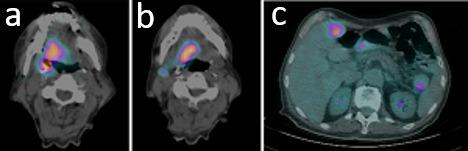

At presentation, isolated metastasis from oropharyngeal squamous cell carcinoma is rare. Liver is a relatively uncommon first site of failure, especially in the absence of other distant metastases, particularly without diagnosis of lung metastases. We report on a case of HPV-related oropharyngeal squamous cell carcinoma with synchronous liver metastasis treated with radiation therapy. This condition, defined as "oligometastatic state," describes a subset of patients with limited volume metastatic disease in whom favorable outcomes were reported with the use of local ablative therapies on both the primary tumor and metastatic sites. As a definitive treatment, we offered the patient, ineligible for other therapeutic approaches, exclusive radiation treatment on the head and neck region and a stereotactic ablative approach targeted to the liver metastasis.

摘要

就诊时,口咽鳞状细胞癌的孤立性转移很少见。肝脏是相对不常见的首个失败部位,尤其是在没有其他远处转移的情况下,特别是未诊断出肺转移时。我们报告了1例接受放射治疗的HPV相关口咽鳞状细胞癌伴同步肝转移的病例。这种情况被定义为“寡转移状态”,描述了一组转移病灶体积有限的患者,据报道,对这些患者的原发肿瘤和转移部位采用局部消融治疗可取得良好疗效。作为确定性治疗,我们为不符合其他治疗方法条件的患者提供了针对头颈部区域的单纯放射治疗以及针对肝转移的立体定向消融治疗。